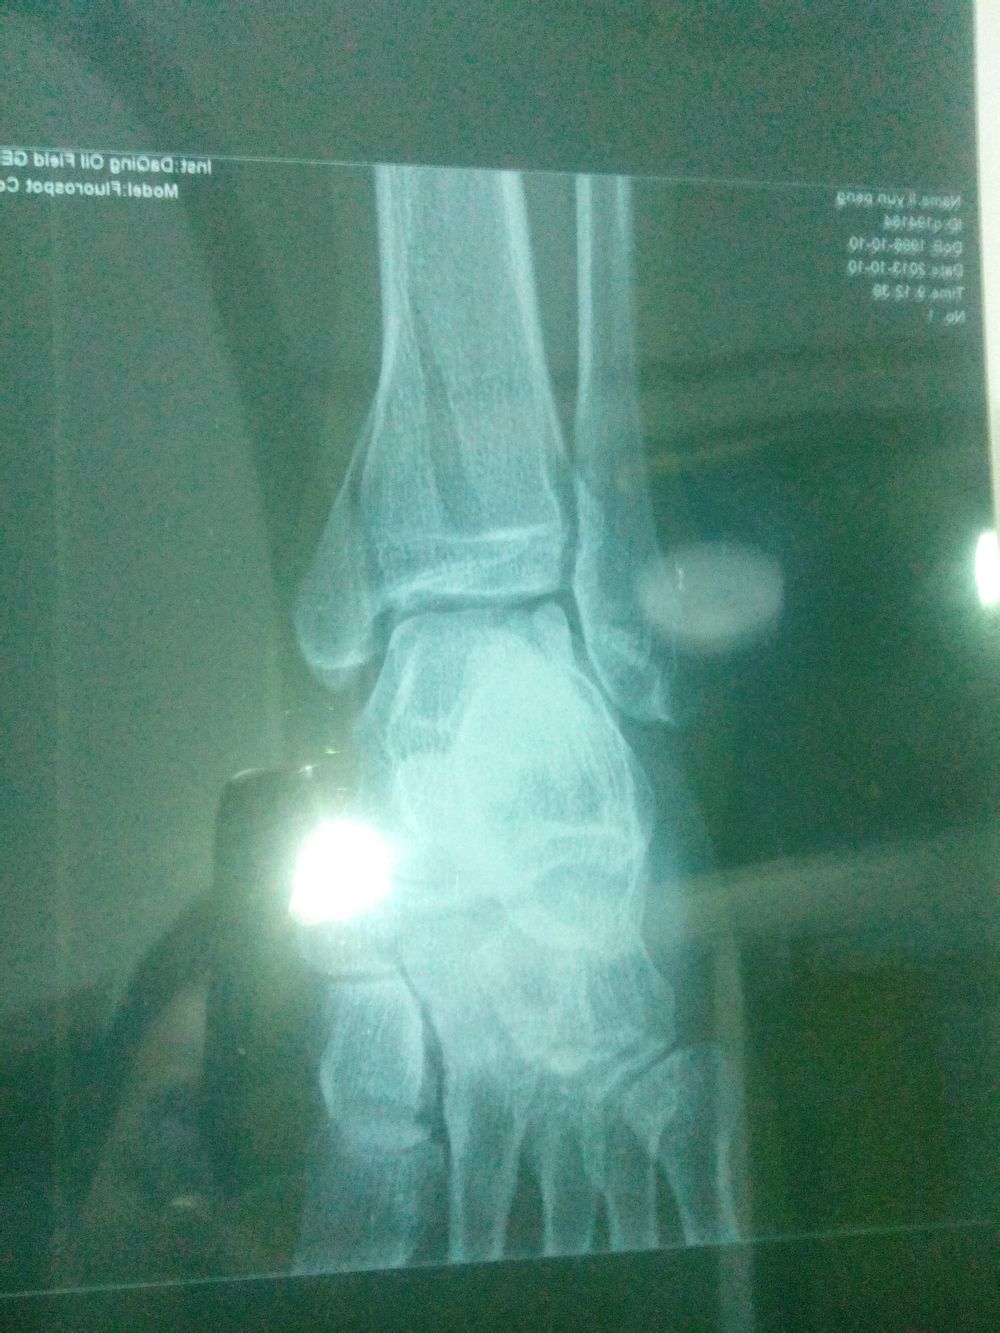

病人: 男 - 66岁 -林源人士 、

病因:蹦跳时脚受伤 -

病情;双脚后跟骨裂 - 左脚两处、 右脚一处 -